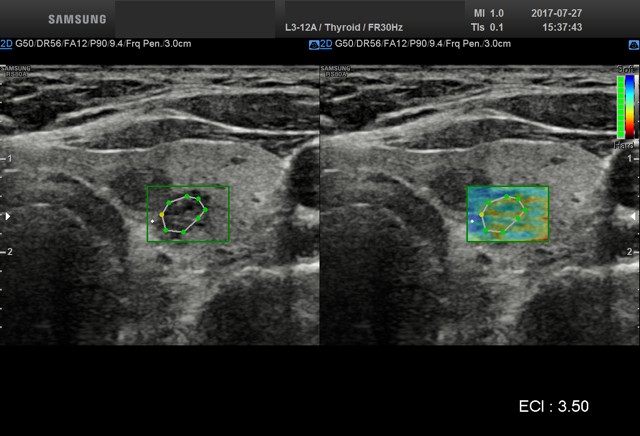

• USG tarczycy

z oceną węzłów, możliwością oceny zmian w elastografii oraz przy użyciu biopsji.

Elastografia.

To przełomowa metoda diagnostyczna wykorzystującą fakt, że chora tkanka zmienia swoją twardość. Można powiedzieć, że elastografia jest cyfrowym rozwinięciem badania dotykiem, kiedy lekarz ocenia twardość i spoistość badanego narządu.

Elastografię proponujemy przede wszystkim w przypadkach:

• podejrzanych zmian w tarczycy

W wielu przypadkach elastografia pozwala uniknąć biopsji i rozwiać wątpliwości co do łagodnego, lub złośliwego charakteru zmiany.

Badanie elastograficzne można wykonać w naszej pracowni jako rozszerzenie badania USG tarczycy i piersi (ocena guzków), a także jako samodzielne badanie – elastografia wątroby w celu oceny włóknienia(stosowana u nas metoda elastrografii 2D-SWE jest znacznie dokładniejsza od dotychczas stosowanej metody TE [FIBROSCAN®].